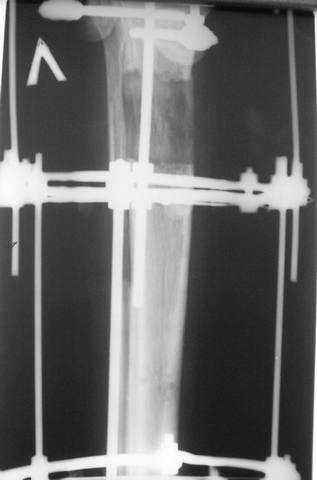

5, 6 - через 2,5 мес после травмы выполнен закрытый остеосинтез блокируемым штифтом.